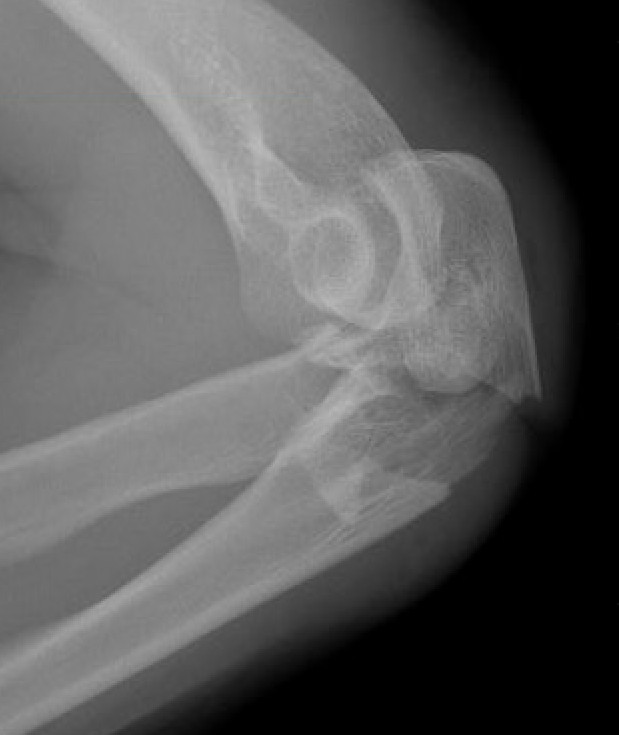

Elbow dislocation + olecranon fracture + radial head/neck fracture +/- coronoid fracture

Complex proximal ulna fracture with radial head replacement subluxation